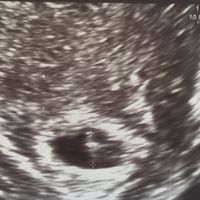

Hola chicas!! Me he decidido a abrir este debate porque veo que muchas os acercáis a mamis julio a preguntarme por el sexo. No soy gine ni nada de eso, eh? Y os aviso de que hay margen de error, pero...

Hola chicas!! Me he decidido a abrir este debate porque veo que muchas os acercáis a mamis julio a preguntarme por el sexo. No soy gine ni nada de eso, eh? Y os aviso de que hay margen de error, pero si os lo tomáis a modo juego estaré encantada de...